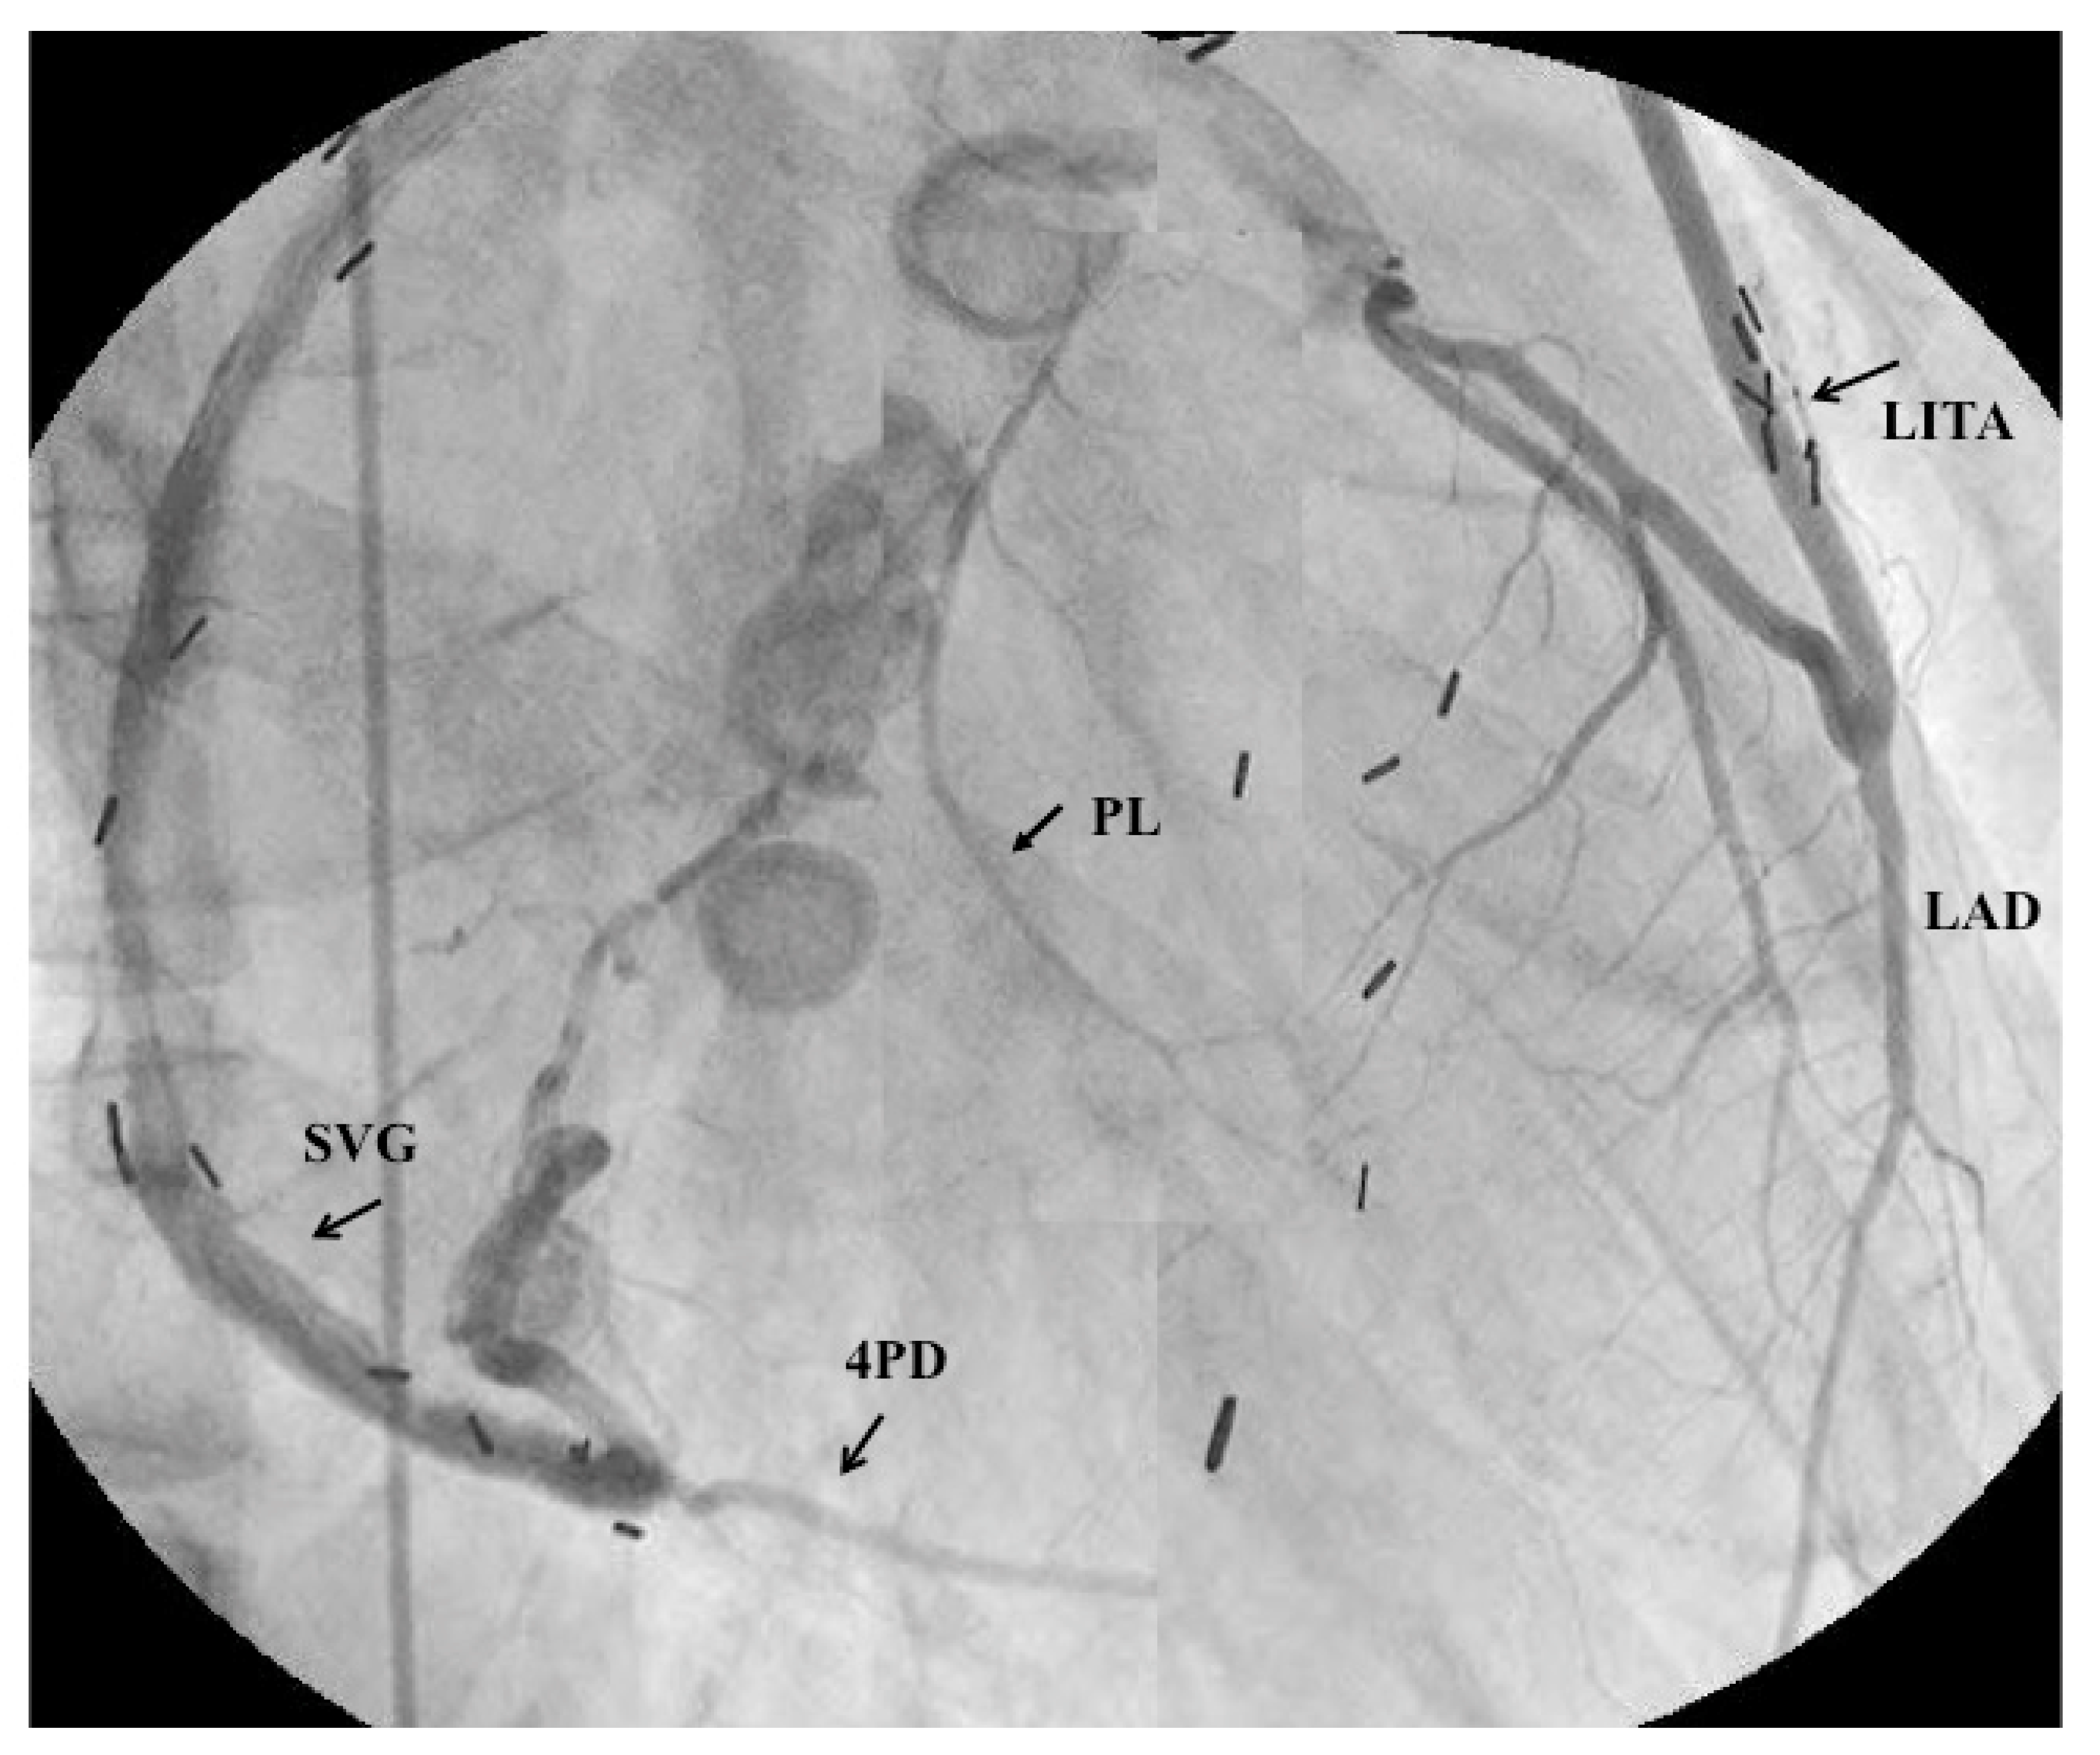

- Tsuda, E.; Kitamura, S.; Kimura, K.; Kobayashi, J.; Miyazaki, S.; Echigo, S.; Yagihara, T. Long-term patency of internal thoracic artery grafts for coronary artery stenosis due to Kawasaki disease: Comparison of early with recent results in small children. Am. Heart J. 2007, 153, 995–1000. [Google Scholar] [CrossRef] [PubMed]

- Tsuda, E.; Kitamura, S. The Cooperative Study of Japan. National survey of coronary artery bypass grafting for coronary stenosis caused by Kawasaki disease in Japan. Circulation 2004, 110 (Suppl. II), II61–II66. [Google Scholar] [CrossRef] [PubMed]

- Kitamura, S.; Tsuda, E.; Kobayashi, J.; Nakajima, H.; Yoshikawa, Y.; Yagihara, T.; Kada, A. Twenty-five-year outcome of pediatric coronary artery bypasss surgery for Kawasaki disease. Circulation 2009, 120, 60–68. [Google Scholar] [CrossRef] [PubMed]

- Matsuura, K.; Kobayashi, J.; Tagusari, O.; Bando, K.; Niwaya, K.; Nakajima, H.; Yagihara, T.; Kitamura, S. Redo off-pump coronary bypass grafting with arterial grafts for Kawasaki disease. Heart Vessels 2006, 21, 361–364. [Google Scholar] [CrossRef] [PubMed]